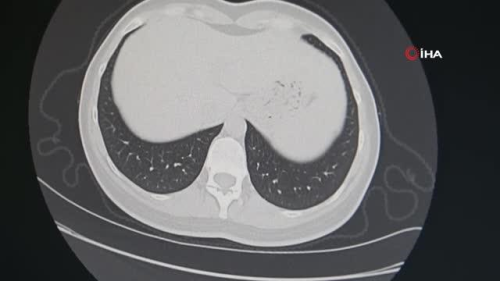

SAMSUN 9 Şubat Dünya Sigarayı-Tütünü Bırakma Günü'nde sigara ve tütün ürünleri kullanımın insan sağlığına verdiği zararlar ve tedavi yöntemleri anlatıldı. Dünya Sigarayı-Tütünü Bırakma Günü kapsamında Medicana İnternational Samsun Hastanesi'nde bir etkinlik düzenlendi. Düzenlenen etkinlikte biorezonans yöntemi ile enerji ölçümü yapıldı. Sigara bağımlısı olan kişilerin yüzde 92'sinin tek seansta sigarayı bıraktığı mora tedavi sürecine dair bilgiler verilerek sağlıklı besinler ikram edildi ve broşür dağıtıldı. Hastane hekimleri, sigara bağımlılığından kurtulmak isteyen vatandaşlara ve sigara kullanımı sonucu akciğer kanseri hastalığına yakalanan kişilere tedavi ve bağımlılıktan kurtulma yolları hakkında bilgiler verdi. Dünyada her 10 saniyede 1 kişinin sigara kullanımına bağlı hastalık nedeniyle hayatını kaybettiğini ifade eden Göğüs Cerrahisi Uzmanı Prof. Dr. Burçin Çelik, "Tütün ve tütün ürünleri kullanımı bir halk sağlığı sorunu. Ülkemizde yapılan çalışmalarda sigara kullanımının ilkokul çağına kadar indiği görülüyor. Sigaranın içinde 4 binin üzerinde kimyasal madde bulunuyor. Bu maddelerden en önemlisi ise nikotin. Sigara nikotin sayesinde psikolojik bağımlılık yanında fizyolojik bağımlılığa da yol açıyor. Dünyada her yıl 6 milyon insan sigara kullanımı sonrası oluşan rahatsızlıklardan dolayı hayatını kaybediyor. Bu her 10 saniyede 1 kişinin hayatını kaybetmesi demektir. Sigara en çok kronik bronşit, koah, damar hastalıkları ve kalp hastalıklarına neden oluyor. Yılda 1,5 milyon kişiye kanser tanısı konuluyor. Kansere yol açan ana etmen de tütün ya da tütün ürünleri. Sigara içenlerde kansere yakalanma riski erkeklerde yüzde 35 oranında, kadınlarda ise yüzde 15 oranında artıyor" dedi. "Kaçak tütünlerin içerisinde ne kadar ve hangi kimyasalın olduğu bilinmiyor" Sigara fiyatlarından dolayı artan tütün kullanımı hakkında da konuşan Prof. Dr. Burçin Çelik, "Sigara zammından sonra halkımız ekonomisini de düşünüyor. Bağımlılık da söz konusu olduğu için tütün ürünlerine yönelen insan sayısı çoğaldı. Tütünleri alıp, sigaraya sarıp o şekilde kullanıyorlar. Özellikle kaçak tütünlerde bu çok sıkıntılı. Çünkü içerisinde ne olduğunu bilmiyorsunuz. En azından fabrikasyon tütünler ya da sigaralarda bir kontrol söz konusu. İçerisindeki kimyasallarda oranlar belli. Kaçak tütünlerde ise bu kimyasallar belli değil. İçerisinde ne olduğunu bilmediğimiz gibi tütün içerken kullanılan kağıt da çok önemli. Kağıdın içerisindeki kimyasal da var olan riski arttırabiliyor. Fabrikasyon mu yoksa el yapımı sigaranın mı daha zararlı olduğunu zaman gösterecek. Sigarayı bırakıp, hayatı bırakmamak lazım. Sigara sadece kanser değil birçok hastalığın riskini arttırır. Evde sigara içilmesi çocuklar için de kötü bir örnek. Sigaranın zararlarının anlatıldığı eğitimin çocukluk çağında öğretilmesi de gerekiyor" diye konuştu. Teknolojinin gelişmesi ile birlikte kanser tanısı konmasında ve tedavisinde büyük ilerleme kat ettiklerinin altını çizen Dr. Çelik, "Akciğer kanserlerinde 15-20 sene önce MR ya da ped değerlendirme ve kanserin nerelerde olduğunu belirlemede geride kalmıştık. Son yıllarda teknolojik gelişmelerle kanser hücrelerinin ya kanserin durumunu çok net tespit edebiliyoruz. Bunla birlikte tedavi hakkında daha doğru kararlar verebiliyoruz. 'bıçak değdi, 2-5 ay sonra öldü' söylemleri 15-20 sene öncesinden günümüze yerleşen söylemler. Şu dönemde bu durum söz konusu değil. Teknolojik gelişmeler, tetkikler ve tahliller hangi hastanın ameliyat olabileceğini, hangisinin olmaması gerektiğini çok daha net gösteriyor. 22 yıldır cerrahım. Mesleğe ilk başladığımda hasta sağ kalım oranı yüzde 50 seviyesindeyken son dönemde akciğer kanseri evre-1 vakalarda bu sağ kalım oranları yüzde 80'lere kadar yükseldi. Bu da çok iyi bir rakam" şeklinde konuştu. "Sigara içtiğiniz zaman 69 tane kanser yapıcı maddeye maruz kalıyorsunuz" Kanser yapıcı maddelerin sigara içerisinde yer aldığına değinen Medikal Onkoloji Uzmanı Prof. Dr. İdris Yücel, "Sigara tiryakiliği çok ciddi bir sağlık sorunu. Sigara kullanımı birçok hastalığın oluşmasına neden olabiliyor. Sigara katranında 69 adet kanser yapan madde var. Bunların arasında aromatik hidrokarbonlar ve radyoaktif maddeler bile var. Sigara içtiğiniz zaman 69 tane kanser yapıcı maddeye maruz kalıyorsunuz. Akciğer kanserlerinin büyük bölümünü sigara içen ya da içmiş kişiler oluşturuyor. O nedenle sigaradan uzak durulması gerekiyor. Sigara içenin de yanında durulmaması gerekiyor. Pasif içicilik de akciğer kanseri riskini arttırır. Akciğer kanserinin 2 ana türü var. Bunlar küçük hücreli ve küçük hücreli olmayan akciğer kanserleri olarak 2'ye ayrılır. Küçük hücreli kanserin tedavisi tıbbi tedavidir. Kemoterapi, radyoterapi ve diğer ilaçlar kullanılır. Küçük hücreli olmayan akciğer kanserinin tedavisi daha çeşitli ve zordur. Erken evrede cerrahi tedavi yapmak gerekir. Cerrahi şansını kaçırmış vakalarda radyoterapi ve kemoterapi kombinasyonları kullanılabilir. İleri derecede vakalarda son dönemde immünoterapiler gündeme geldi. İmmünoterapi ilaçlarının ruhsatı Türkiye'de vardı ama geri ödemesi yoktu. Resmi Gazete yayımlanan karar ile birlikte en çok kullanılan immünoterapi ilacının geri ödemesinin yayınlandığını duyduk. Bu durum biz onkolokları ve hastaları çok sevindirdi" ifadelerini kullandı. "Mora terapi ile tek seansta sigara bırakanların oranı yüzde 92" Sigara bırakma konusunda kullanılan tedavi yöntemleri hakkında açıklamalarda bulunan Göğüs Hastalıkları Uzmanı Dr. Özgür İnce ise şunları söyledi: "Sigara, akciğer kanseri ve koah gibi ölümcül akciğer hastalıklarının başta gelen sebebidir. Akciğer haricinde kalp ve beyin damar hastalıklarının da önde gelen sebeplerindendir. Sigara bırakmak için çeşitli yöntemler vardır. Nikotin replasmanı tedavileri, iki üç çeşit ilaç, akupunktur, hipnoz ve biorezonans yöntemleri kullanılabilmektedir. Sigara bıraktırma kliniğimizde 10 yılı aşkın bir zamandır tüm bu tedavi yöntemleri kullanılmış ve en başarılı yöntem olan mora terapi (radyofrekans) yöntemi olmuştur. Sigara bağımlılığı kabaca kimyasal (nikotin) bağımlılık ve sosyal-psikojenik bağımlılık olarak 2 kısımdan oluşur. Kimyasal bağımlılığı radyo frekans ile rahatlıkla tedavi edebilmekteyiz. Sosyal bağımlılık için de hastalarımızla yaklaşık 30-40 dakika süren bir eğitim ve bilgilendirme konuşması sayesinde yüzde 92'ye varan bir başarı elde etmekteyiz. Mora terapinin herhangi bir yan etkisi veya kontrendike durumu yoktur. Genellikle tek seans yeterlidir ancak gerekirse pekiştirmeler yapılabilmektedir. Seans süresi 1 saat kadardır. Seans esnasında eller ve ayak tabanları metal levhalara temas eder, herhangi bir ağrı acı söz konusu değildir. Radyasyon, manyetik alan, kimyasal madde içermez. Radyo dalgaları ile çalışır ve otomobilde radyo dinlemek ne kadar zarar verirse o kadar zarar verebilir. Bunun yanında diğer tüm yöntemlerle kıyaslandığında daha başarılı ve daha az yan etkili bir yöntemdir. Dünya Sağlık Örgütü sigara bağımlılığını 'hastalık' olarak kabul ediyor. Kendi kendine bırakmaya çabalamak çok güzel bir şeydir. Ama onunda istatistiklerine baktığımız zaman yüzde 5'ten daha yukarı bir başarı olmuyor. Mutlaka bir profesyonel destek öneriyoruz. "